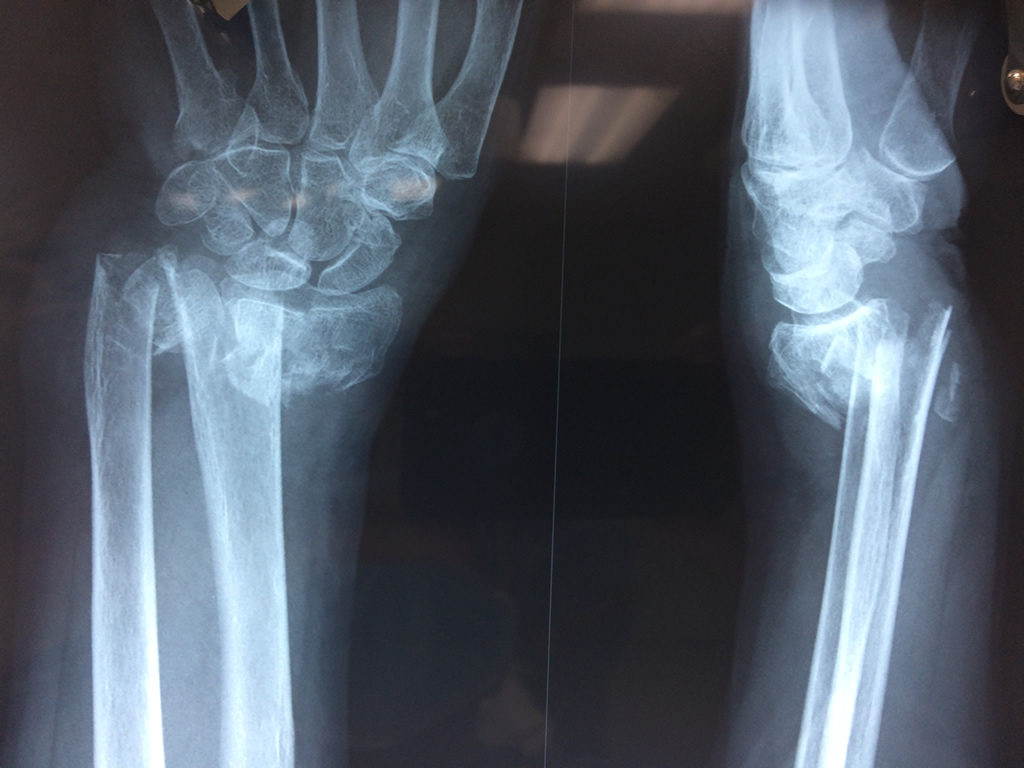

Cirugía de Muñeca y Mano

Los procedimientos más comunes en cirugía de la mano son aquellos destinados a reparar traumatismos, incluyendo lesiones de tendones, nervios, vasos sanguíneos, y articulaciones; huesos fracturados; y quemaduras, cortes, y otros daños de la piel.